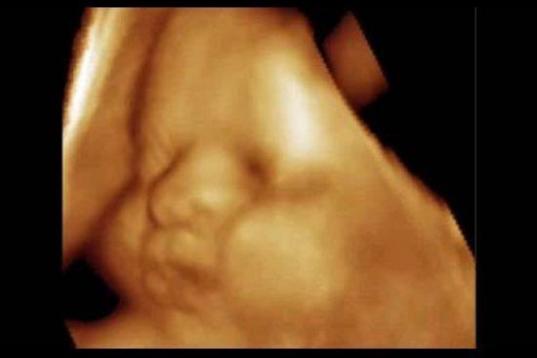

En esta galería puedes ver en fotos como es el desarrollo de un feto de semana en semana:

Desarrollo del feto, en fotos